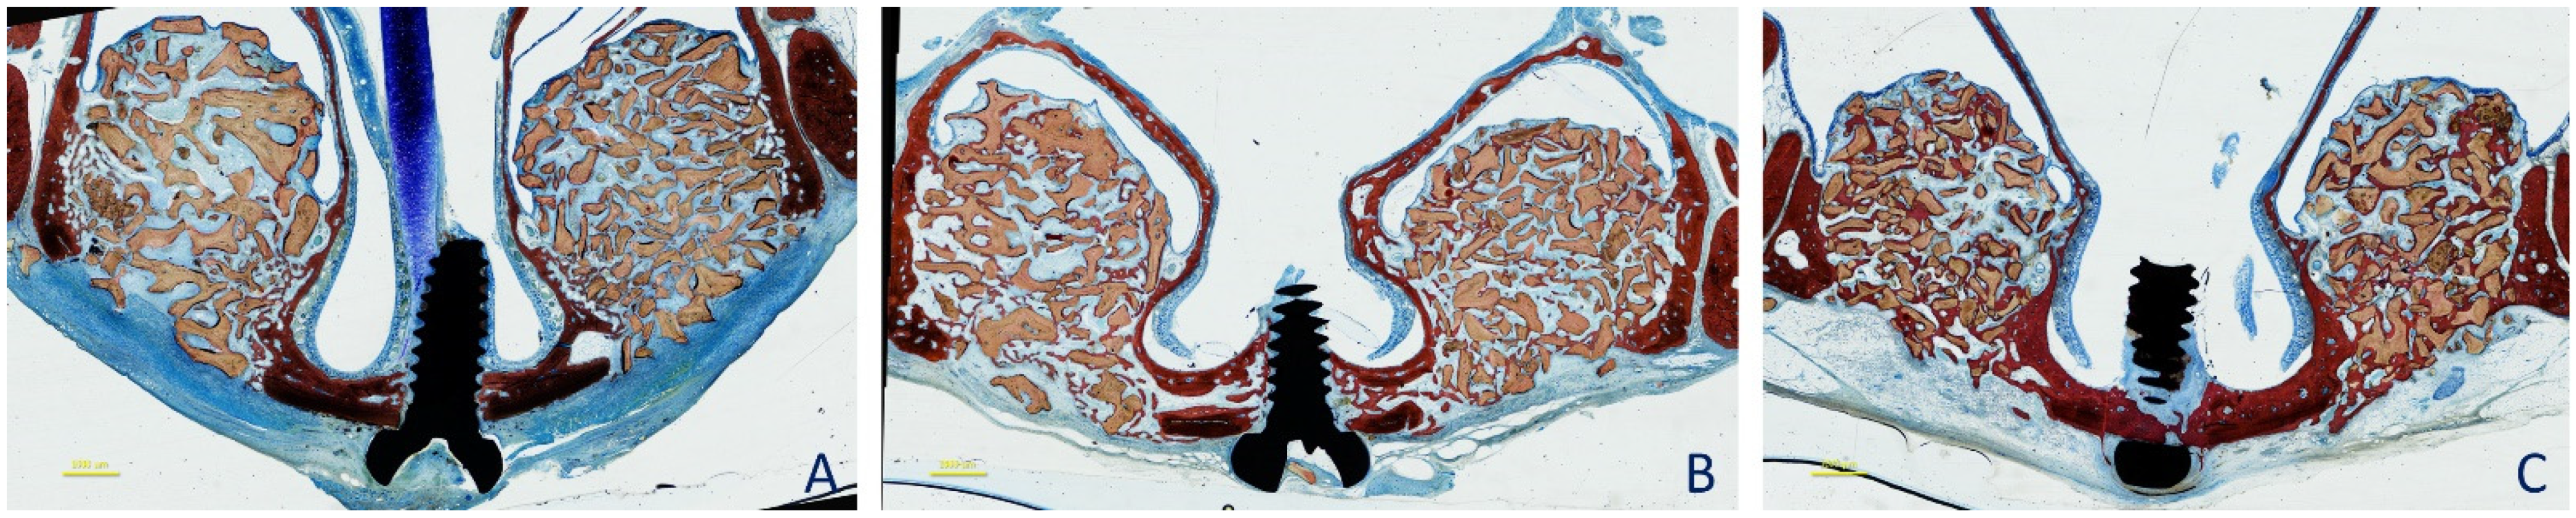

2.3. Surgical Procedures

2.5. MicroCT Evaluations

3. Results